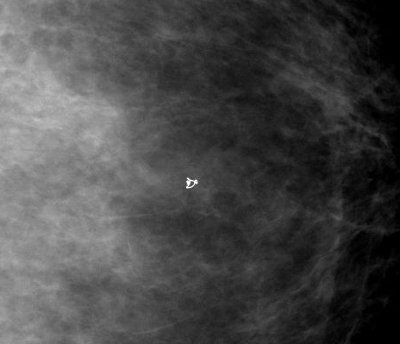

Il est laissé en place un clip pour guider le chirurgien avant une éventuelle intervention (clip qui pourra rester en place s'il n'y a pas d'intervention).

Clip post-biopsies Vérification per-opératoire du clip dans la tumorectomie (le clip est présent dans la pièce opératoire)